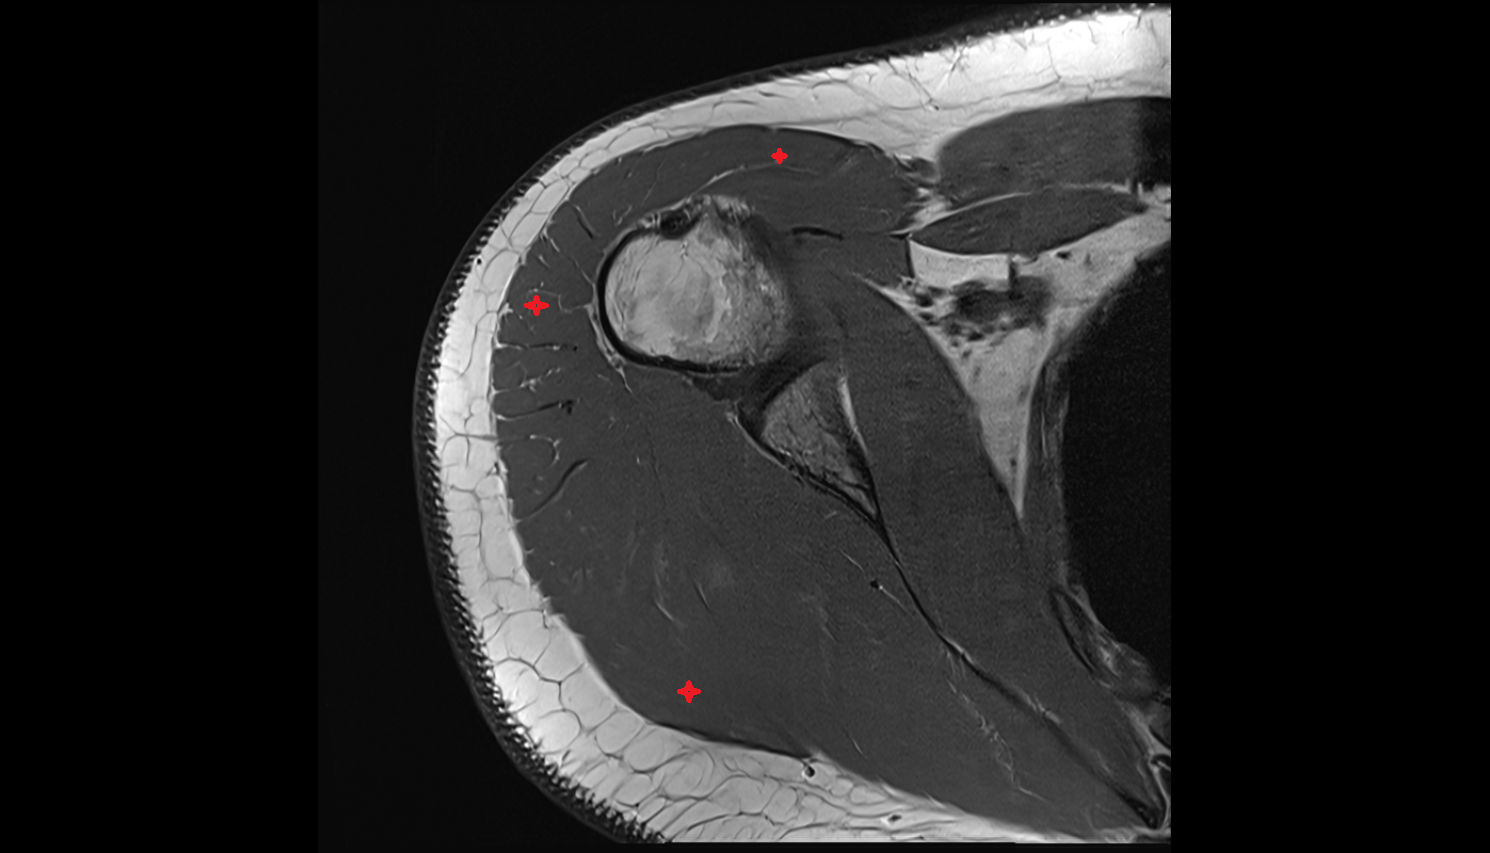

- Deltoid muscle

- Subscapularis tendon

- Glenoid labrum

- Adipose tissue (Shoulder)

- Subacromial space